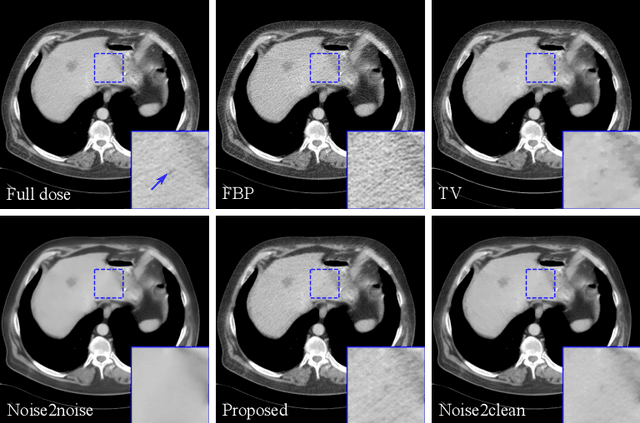

Deep neural networks have been proved efficient for medical image denoising. Current training methods require both noisy and clean images. However, clean images cannot be acquired for many practical medical applications due to naturally noisy signal, such as dynamic imaging, spectral computed tomography, arterial spin labeling magnetic resonance imaging, etc. In this paper we proposed a training method which learned denoising neural networks from noisy training samples only. Training data in the acquisition domain was split to two subsets and the network was trained to map one noisy set to the other. A consensus loss function was further proposed to efficiently combine the outputs from both subsets. A mathematical proof was provided that the proposed training scheme was equivalent to training with noisy and clean samples when the noise in the two subsets was uncorrelated and zero-mean. The method was validated on Low-dose CT Challenge dataset and NYU MRI dataset and achieved improved performance compared to existing unsupervised methods.